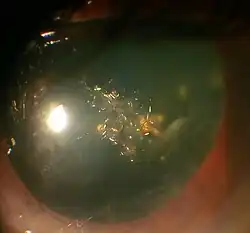

Posterior polar cataract of an 8-year-old boy in left eye

Posterior polar cataract of an 8-year-old boy in left eye -